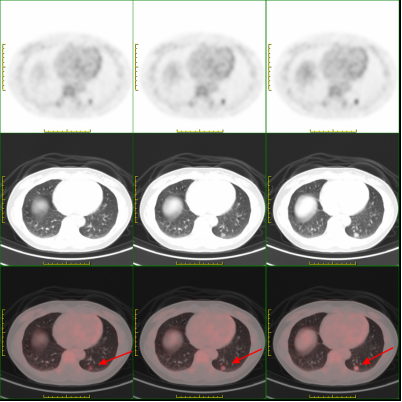

近期,李女士在体检时发现,其肺部存在一个直径约1.1厘米的压实性结节影,并且该结节形态欠规则,边缘模糊。当地医院临床医生高度认为该结节为恶性肿瘤。吓坏了的李女士为得到准确诊断,来到了市四医院核医学科进行了PET/CT检查。对照PET/CT图像,医务人员仔细辨别后,认为其为炎性病变。后经病理检查,证实了医务人员的判断。看到恶性肿瘤被排除的检查结果,压在李女士心头的大石头总算落了地。